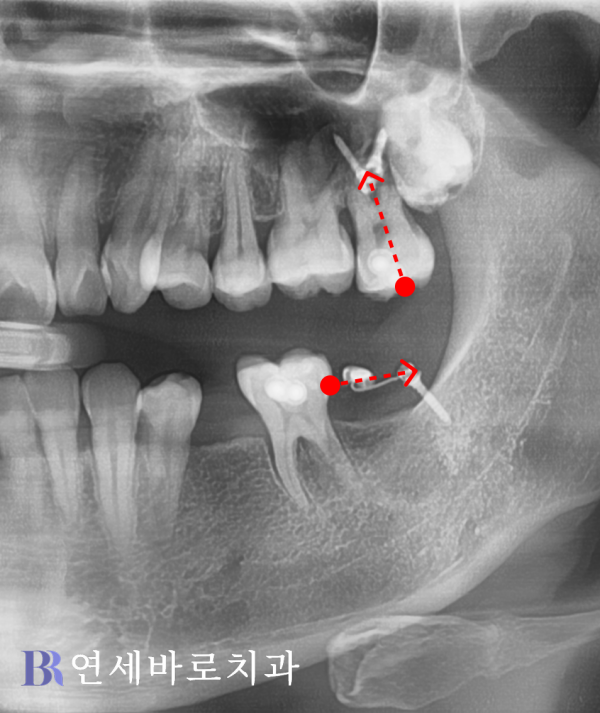

쓰러진 어금니를 바르게 세워

올바른 각도로 일으켜주었고,

상악 대합치를 위로 올려주는

상방견인이 이루어졌습니다.

환자분께서는 기존 영구치를

전혀 손상시키지 않으면서

임플란트가 성공적으로

완성됐다는 점에 가장 큰

만족스러움을 느끼셨습니다.

하악 어금니는 물론이거니와,

대합치까지 온전한 상태로

안전하게 보존하였습니다.